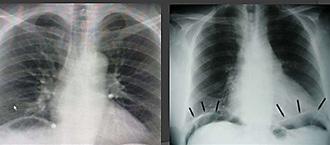

Derrame pericárdico severo da imagen en botellón en la radiografía de tórax. (ENAM EXTRA 2021)

Confirman el diagnóstico pues detectan un pericardio engrosado, con frecuencia calcificado, las imágenes de elección son: la tomografía o resonancia magnética (cabe resaltar el diagnóstico diferencial con la miocardiopatía restrictiva).